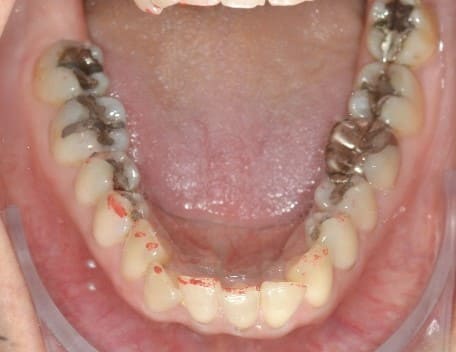

Initial